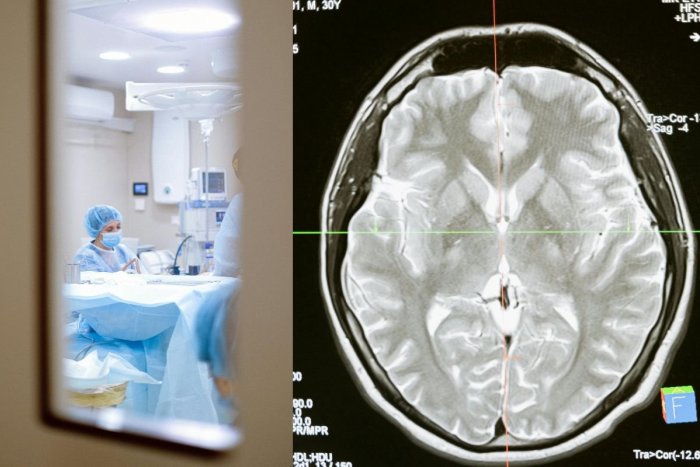

Ilustračný obrázok k článku MŔTVICA ohrozuje aj deti! Adamka (8) zachránili na poslednú chvíľu

Zdroj: Pexels.com , Pexels.com

Presvedčili sa o tom aj rodičia 8-ročného Adamka. Magnetická rezonancia v jeho prípade ukázala, že má pretrhnutú jednu z ciev v mozgu. Chlapca z Ostravy okamžite po tomto odhalení previezli na sálu.

Do mozgu mu zaviedli stent, ktorý mu cievu „zalepil“. Záchrana prišla práve v čas.